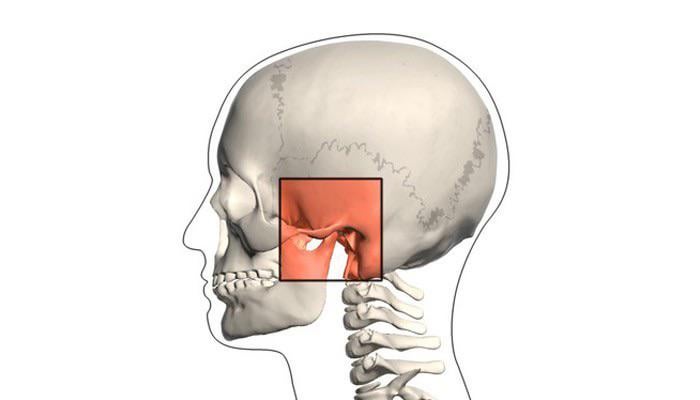

*l’immagine mostra l’articolazione con cui ho un problema. per tutte le persone sane con le articolazioni che non stanno ancora scoppiando – per favore non restare a bocca aperta quando sbadigli, non aprire la bocca più di 2 dita nella tua routine quotidiana, se non ti piace l’opera, mastica meno chewing gum e passa alle mentine; mi ringrazierai più tardi!